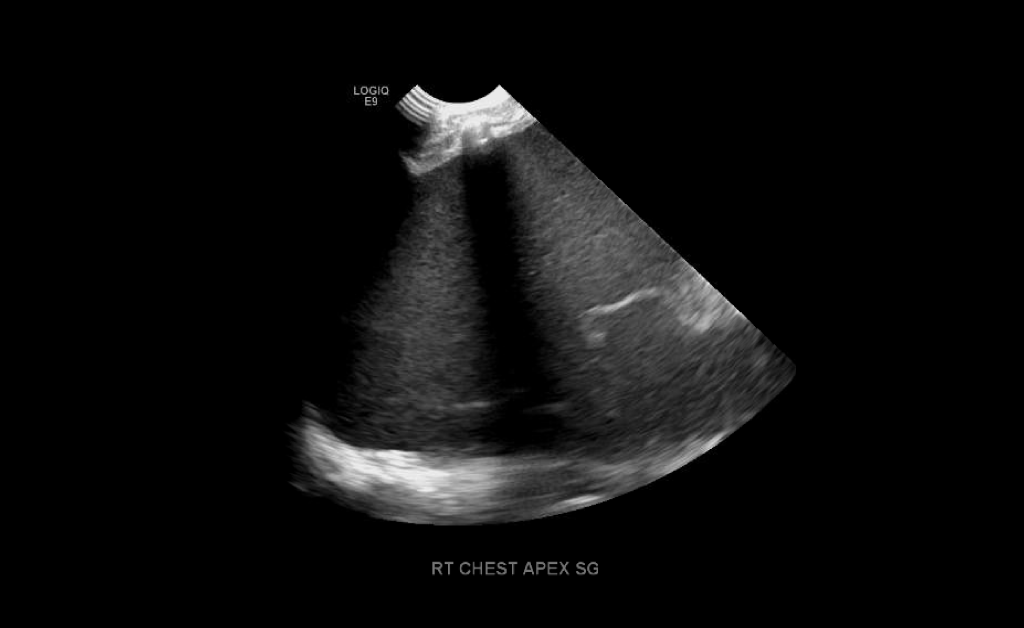

Large volume pleural effusion

Large volume echogenic pleural effusion

Large and or symptomatic pleural effusions may be treated with ultrasound guided thoracentesis which can double as a diagnostic procedure, where the fluid removed can be sent to pathology. Normal analysis of the fluid consists of cytology, chemistry and culture.